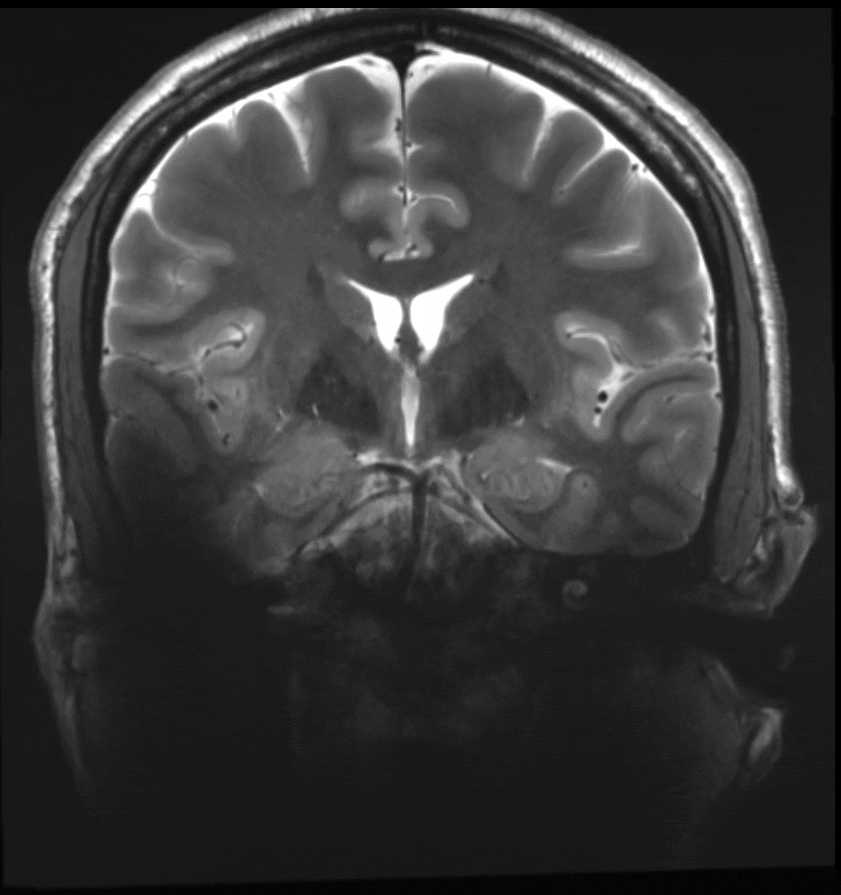

A T2-TSE image using both the Tac G2 coil and the Nova Medical coil. Areas of signal dropout in the temporal lobe are visible in the scans acquired with the Nova coil.